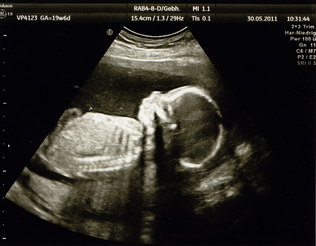

Ultraschall (Sonographie)

In der Frauenheilkunde und Geburtshilfe werden Ultraschalluntersuchungen durch die Bauchdecke (Abdominalsonographie) und durch die Scheide (Vaginalsonographie) durchgeführt. Bei der Vaginalsonographie wird eine dünne Ultraschallsonde in die Scheide eingeführt, diese Art der Untersuchung ist vollkommen schmerzlos.

In der Frühschwangerschaft (etwa bis zur 12. SSW) wird hauptsächlich die Vaginalsonographie durchgeführt. Später erfolgt der Ultraschall nur mehr durch die Bauchdecke. Sämtliche Angaben bzgl. Schwangerschaftswochen beziehen sich immer auf den ersten Tag der letzten Regel.